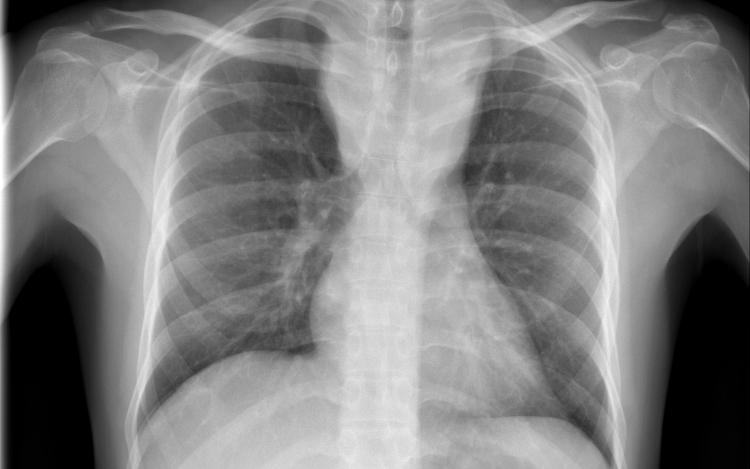

Forrás: mti - illusztráció

Tüdőrákban halt meg egy szervátültetett, aki egy erős dohányos tüdejét kapta meg

Tüdőrákban halt meg a transzplantáció után másfél évvel egy francia nő, akibe egy hajdan erős dohányos nő tüdejét ültették át.

A gyermekkora óta cisztás fibrózisban szenvedő páciens 2015 novemberében kapta meg a sokáig erősen dohányzó nő tüdejét, 2017 júniusában pedig bekerült a montpellier-i egyetemi klinikára, ahol két hónappal később elhunyt tüdőrákban, anélkül, hogy bármiféle terápiát alkalmazhattak volna nála. A tanulmány szerint a páciens a dohányzás okozta tüdőrák jellegzetes tüneteit mutatta.

A transzplantáció és a tüdő első rendellenességeinek röntgen általi észlelése közti rövid idő arra utal, hogy a tüdőrák már a donornál keletkezett, a szervkilökődés megakadályozására szedett immungyengítő gyógyszerek pedig csak felgyorsították a kifejlődését.